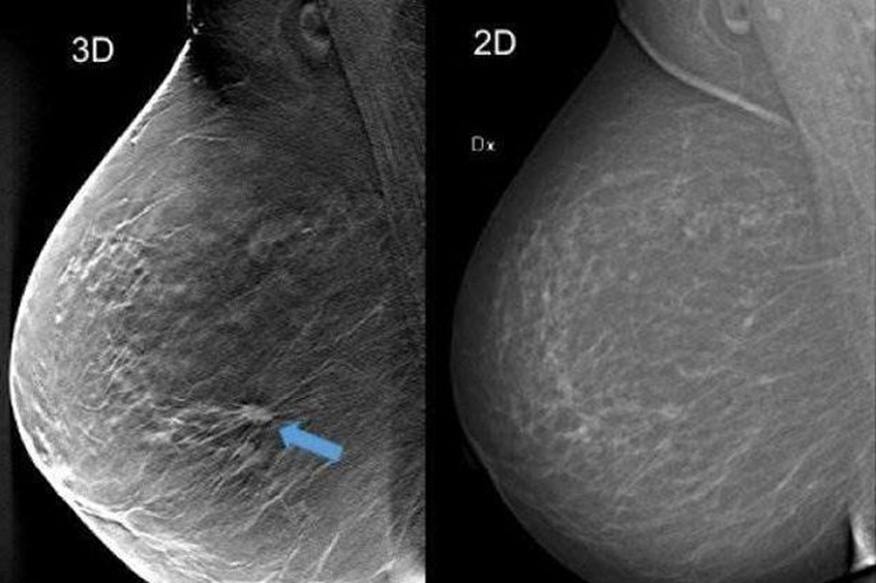

mammografia e tomosintesi

Oggi il cancro della mammella è considerato uno dei tumori più guaribili, con tassi di sopravvivenza a 5 anni superiori all’85%. Nessun altro tumore solido ha testimoniato negli ultimi 30 anni un simile progresso nel miglioramento prognostico con un profondo mutamento negli approcci terapeutici. La maggior parte delle donne con cancro della mammella può essere trattata con terapie conservative, ovvero senza gravi mutilazioni, e con farmaci sempre più mirati.